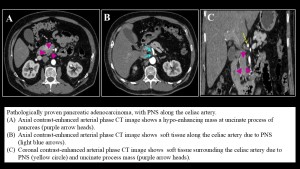

Pancreatic cancer

The tendency of pancreatic cancer to spread along nerves is likely attributable to the dense network of neural plexuses surrounding the pancreas. In pancreatic ductal adenocarcinoma, the most frequent sites of perineural spread are the celiac plexus and the plexus pancreaticus capitalis . Except for the celiac ganglia, the neural plexuses are not directly visualized at imaging, with the mesenteric arteries they follow serving as surrogate landmarks for detection, where PNS manifest as wispy increased attenuation or confluent perivascular soft tissue.